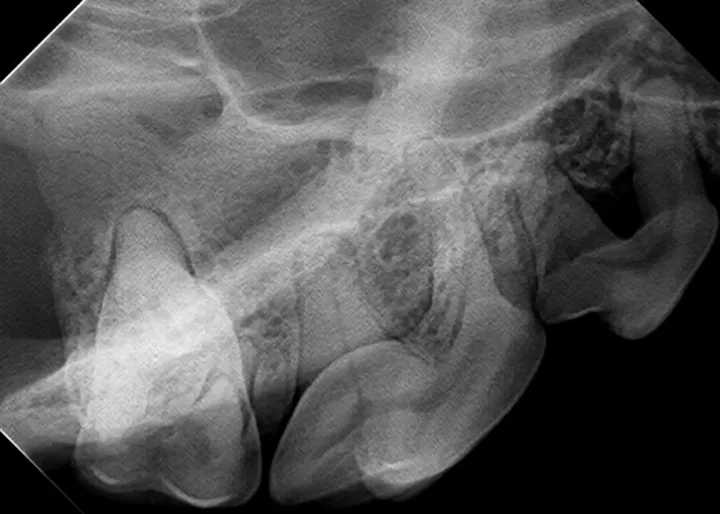

The relatively simple parallel technique is used to image the mandibular caudal cheek teeth on small dogs and cats.

For large dogs, use this technique to image teeth from the third premolar to the last molar. This portion of the oral cavity has room enough to place the sensor parallel and adjacent to the desired teeth, on the lingual aspect of the mandible. Then, aim the tube head perpendicular to the sensor.

For example, image the caudal cheek teeth in the maxilla with the tube head at a 60° angle from the horizon.2 When the patient is positioned with the maxilla parallel to the horizon, the sensor can also be placed parallel to the horizon (ie, inside the oral cavity and adjacent to the desired teeth), making it much easier to visualize the angle.

Place the sensor horizontally inside the oral cavity, with the cusp tip of the desired teeth at the edge of the sensor. Placing the sensor inside the oral cavity will provide enough room to catch the radiograph image.

Radiographs should be taken in the same order each time. Starting with the right maxillary molars, move the sensor and tube head around the entire arch until the left caudal maxilla is reached. Then, position the patient in ventral recumbency and repeat the process, starting with the left mandibular molars. Continue around the arch until the right caudal mandible is reached. This sequence is suggested because full-mouth-series templates included in most digital software programs are arranged in this order and will result in the mirror image for correct viewing of radiographs.